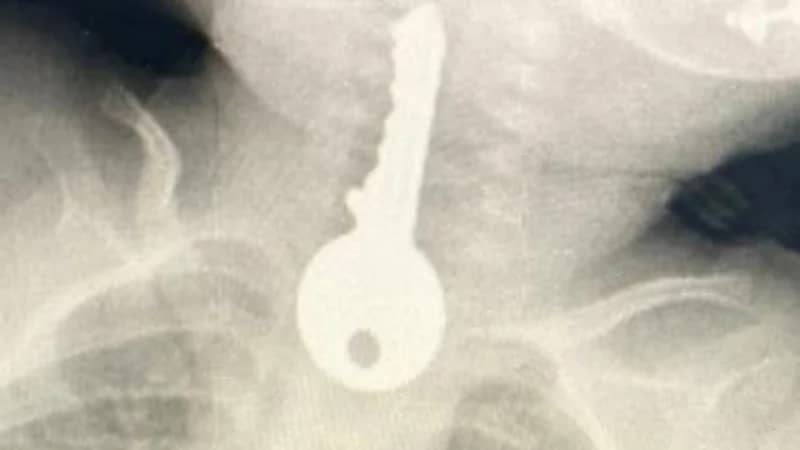

تمكن فريق طبي في محافظة الطائف من إنقاذ طفل كاد أن يفارق الحياة بعد وصوله الطوارئ في حالة حرجة إثر ابتلاعه مفتاح

وقال مجمع الملك فيصل الطبي عبر حسابه في تويتر، أنه استقبل حالة طفل في وضع صحي حرج يعاني من ضيق في التنفس، مما استدعى تقديم الإسعافات الأولية وإجراء الفحوصات السريرية والإشعاعية.

وكشفت الفحوصات وجود جسم غريب على شكل مفتاح في المريء، وعليه تم إجراء عملية بالمنظار للطفل وإخراج المفتاح